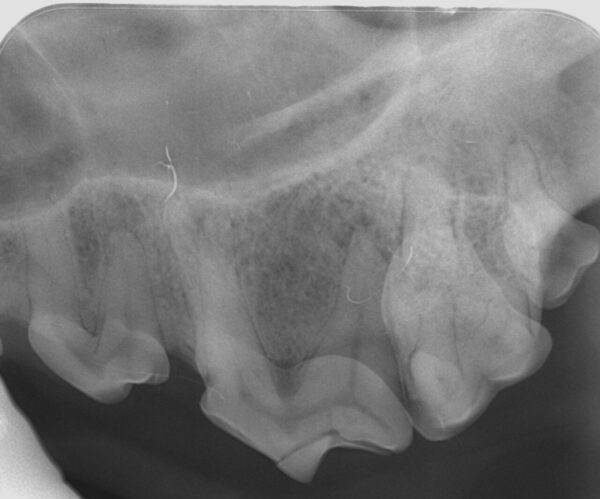

Fracturas dentales

Las radiografías son esenciales en la detección y evaluación de las fracturas del hueso (alveolar, maxilar y mandibular) y del diente (tanto a nivel de la corona, para ver su relación con la pulpa, como de la raíz dental). Los dientes rotos o fracturados son un problema muy común en la práctica veterinaria.

El tratamiento, a menudo, depende de qué partes del diente estén afectadas, raíz y/o corona, y en el caso de esta última, de qué capa(s): esmalte, dentina y si hay exposición o no de la pulpa:

- Las fracturas que no afectan directamente el sistema del conducto radicular se denominan fracturas de corona no complicadas, aunque hay que tener en cuenta que la exposición de los túbulos dentinarios de la dentina puede actuar como vía de entrada de gérmenes y también originar las alteraciones endodónticas (imagen 20).

- Las fracturas que exponen el canal radicular se denominan fracturas complicadas y estos dientes con exposición directa de la pulpa deben tratarse mediante endodoncia o extracción (imágenes 21 y 22).

Cuando la fractura afecte a la raíz del diente este debe ser extraído (imagen 23).